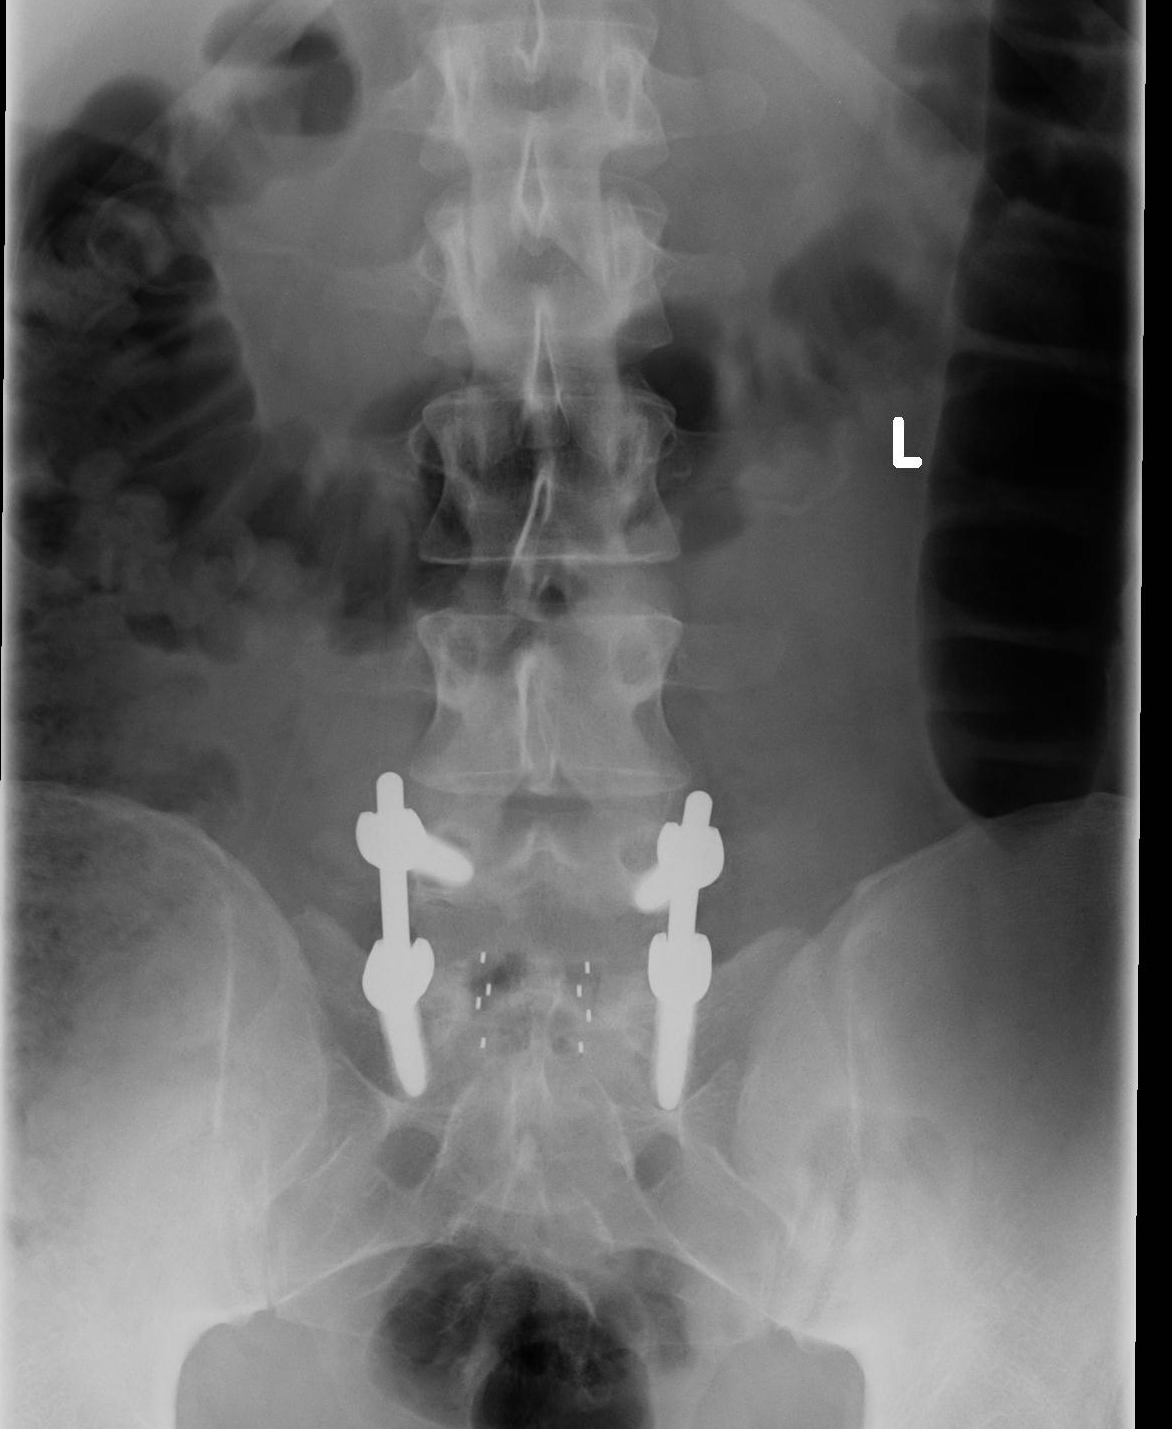

My wife and a friend picked me up for the ride. A spine fusion surgery involves using bone graft to cause two vertebral bodies to grow together into one long bone. Good afternoon, i am preparing for an l4/l5/s1 fusion, both anterior and posterior minimally invasive procedure using bmp cages to replace the disk and 6 screws with 2 rods.

Pain 10 years after a spinal fusion l5/s1. Bone graft can be taken from the patient�s hip (autograft bone) during the spine fusion surgery, harvested from cadaver bone (allograft bone), or manufactured. Good afternoon, i am preparing for an l4/l5/s1 fusion, both anterior and posterior minimally invasive procedure using bmp cages to replace the disk and 6 screws with 2 rods.

What to do if i had surgery (tlif l4 5 l5 s1) and recently found out that what to do if i had a failed fusion.? answered by dr. Lower back pain a year after l5 s1 surgery. L5 s1 fusion is major surgery whereby the l5/s1 disc is removed and the l5 and s1 spinal bones are stabilized by hardware.